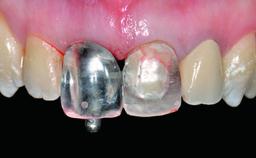

Replacement of a Missing Upper Left Central Incisor: Late Placement of an RC Bone Level Implant, CAD/CAM Zirconia Abutment

A healthy 37-year-old female patient was referred for a consultation on the replacement of missing tooth 21 with an implant-supported restoration. She stated that several years previously the tooth had been traumatically avulsed following a motor vehicle accident. The tooth was replaced with a three-unit fixed partial denture (FPD) immediately afterwards. Over time, she became disillusioned with the FPD and looked for a different option, including orthodontic therapy. She presented still in her orthodontic appliances, with the pontic sectioned free from the FPD but attached to the archwire. Her orthodontist felt that orthodontic treatment had been successfully completed, but nevertheless referred her before removing the appliances in case adjustments were necessary.

Abutment Type CAD/CAM

Prosthesis Type FDP